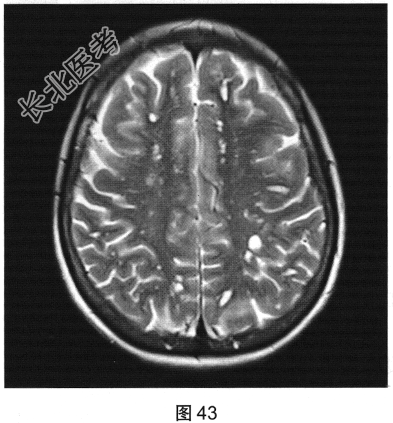

- 多项选择题2.[提示]患者行FLAIR、DWI及增强扫描,见图45~图54。该患者MRI影像的主要阳性表现有( )

A、增强后扫描病灶无强化

B、病灶呈簇状分布,形态规则,边界清楚

C、双侧放射冠及半卵圆中心多发条状、圆形及卵圆形异常信号灶

D、病灶呈长T1、长T2信号,FLAIR为低信号,DWI为高信号,ADC为低信号

E、病灶呈长T1、长T2信号,FLAIR为低信号,DWI为低信号,ADC为高信号

F、病灶呈长T1、长T2信号,FLAIR为稍高信号,DWI为低信号,ADC为高信号

G、增强后扫描病灶轻度强化